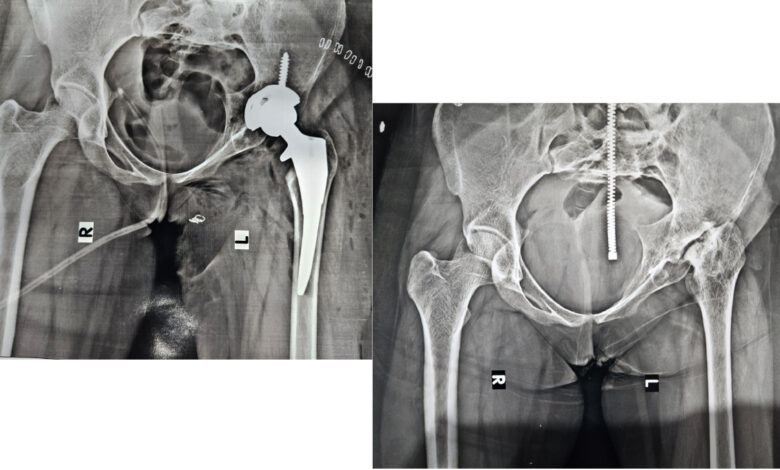

दैनिक स्थैर्य । 23 मे 2025। फलटण । येथील जोशी हॉस्पिटल येथे नुकतेच 15 वर्षाच्या रुग्णांवर यशस्वीरित्या सांधेरोपण केल्यानंतर पुन्हा 19 वर्षाच्या मुलीवर खुब्याचे यशस्वीरित्या कृत्रिम सांधेरोपण केल्याची माहिती जोशी हॉस्पिटलचे डॉ. प्रसाद जोशी यांनी दिली.

डॉ. प्रसाद जोशी म्हणाले, वयाच्या 5 वर्षापासून तिला Perthes disease हा आजार जडला होता. या आजारामुळे खुब्याच्या बॉलचा रक्त पुरवठा कमी पडून तो हळूहळू खराब होऊ लागतो. यापूर्वी तिची 2 ऑपरेशन्स दुसर्या हॉस्पिटलमध्ये आधी झाली होती. परंतु दुर्दैवानीने खुब्याचा सांधा हळूहळू पूर्णपणे खराब होऊन गोळा पूर्ण विरघळा होता. वाटी पूर्णपणे बुजून गेली होती. हे ऑपरेशन अत्यंत अवघड व गुंतागुंतीचे होते. वाटीचे हाड शोधून त्यामध्ये नवीन वाटी बसवणे गरजेचे होते. या रुग्णाची कोवळी हाडे खोवताना खूप काळजीपूर्वक ऑपरेशन केले गेले. सिरॅमिक ऑन पॉली हा Uncemented सांधा या रुग्णामध्ये बसवण्यात आला. पायाची उंची 3 सेंटीमीटरने कमी होती. ती सुद्धा पूर्ववत दुसर्या पायाइतकी करण्यात टीमला यश मिळाले. अशी अवघड शस्त्रक्रिया शहरातील मोठ्या हॉस्पिटलमध्ये करण्यात येते. अशा प्रकारची शस्त्रक्रिया जोशी हॉस्पिटल मध्ये पहिल्यांदाच यशस्वीरित्या करण्यात आली. हा रुग्ण आता पुढील आयुष्य यशस्वीरित्या जगेल. सर्व हालचाली व कामे उत्तमरित्या करू शकेल, असे विश्वासपूर्ण डॉ. प्रसाद जोशी यांनी सांगितले.